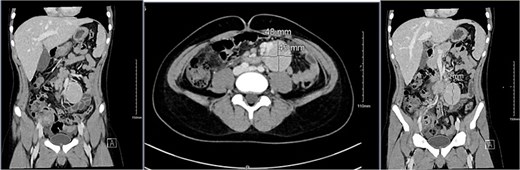

Imaging studies included abdomen/KUB X-ray was unremarkable (Fig. 1). An abdominal ultrasound, which showed a hypoechoic mass in the left lower abdomen and minimal free fluid (Fig. 2). A computed tomography (CT) scan of the abdomen revealed an appendicular abscess and a soft tissue mesenteric mass measuring 6 × 4 cm (Fig. 3).

A CT scan of the abdomen revealed an appendicular abscess measuring ⁓40 mL with an associated appendicolith and a soft tissue mesenteric mass measuring 6 × 4 cm, accompanied by enlarged mesenteric lymph nodes.